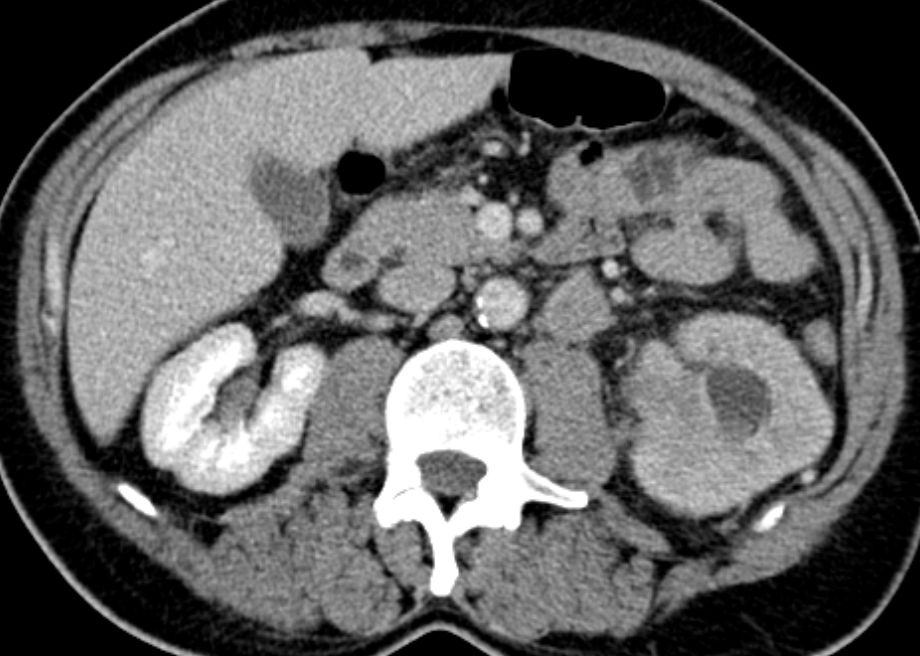

| CT | 81-jährige Frau mit einem großen, die linke Niere einnehmendem

Tumor. Histologie: Urothelkarzinom.![]() | |||

Die linke Nierenarterie ist von LK-Metastasen eingeschlossen.![]() | ||||